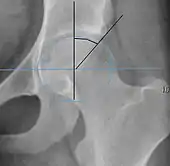

Projectional radiography ("X-ray")is often considered first line for FAI.[10] Anterior-posterior pelvis and a lateral image of the hip in question should be attained.[10] A 45-degree Dunn view is also recommended.[10][19]

| Alpha angle | ![]() |

Degree of bulging of the femoral head-neck junction: In normal conditions there is a symmetric concave contour at the junction of the femoral head and neck. Loss of this concavity or bone bulging may lead to cam type impingement. The degree of this deformity can be measured by the alpha angle. Although it can be measured in the cross-lateral view, the 45° Dunn view is considered more sensitive and the frog leg view more specific in determining pathologic values. |

|